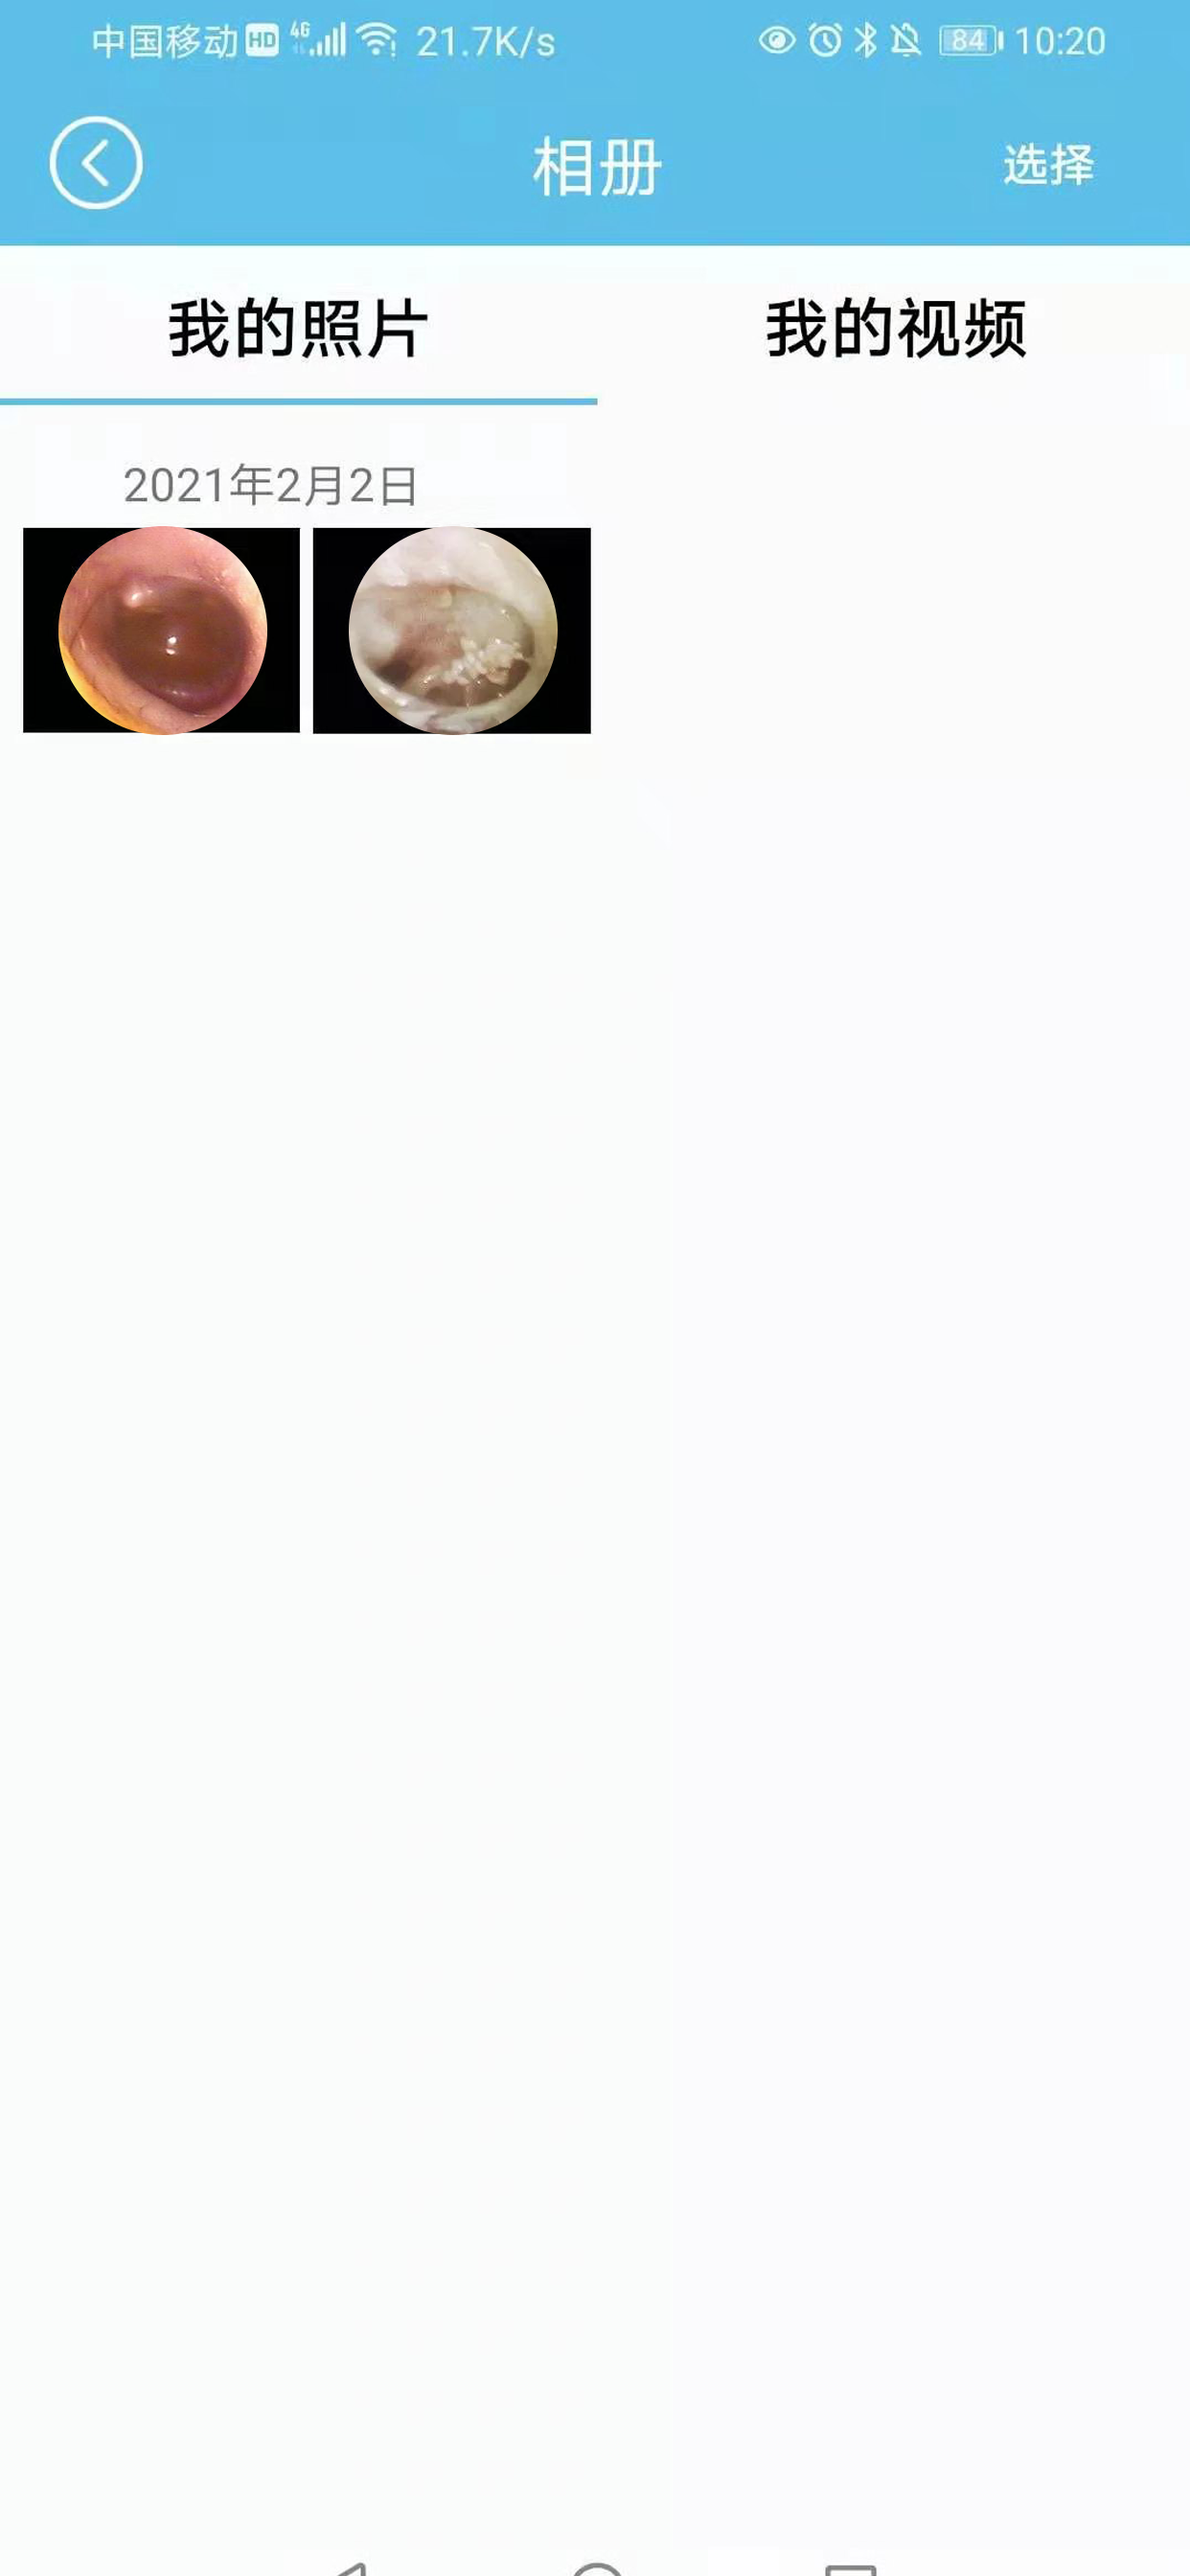

本应用定义为一个典型的无线可视采耳设备APP软件。它将实现连接wifi主设备、无线图像显示、拍照、录像、图库、广角、聚焦、陀螺仪、左耳右耳、横竖屏调节、菜单等功能,以配合设备端实现用户达到享受性、可视性采耳功能。